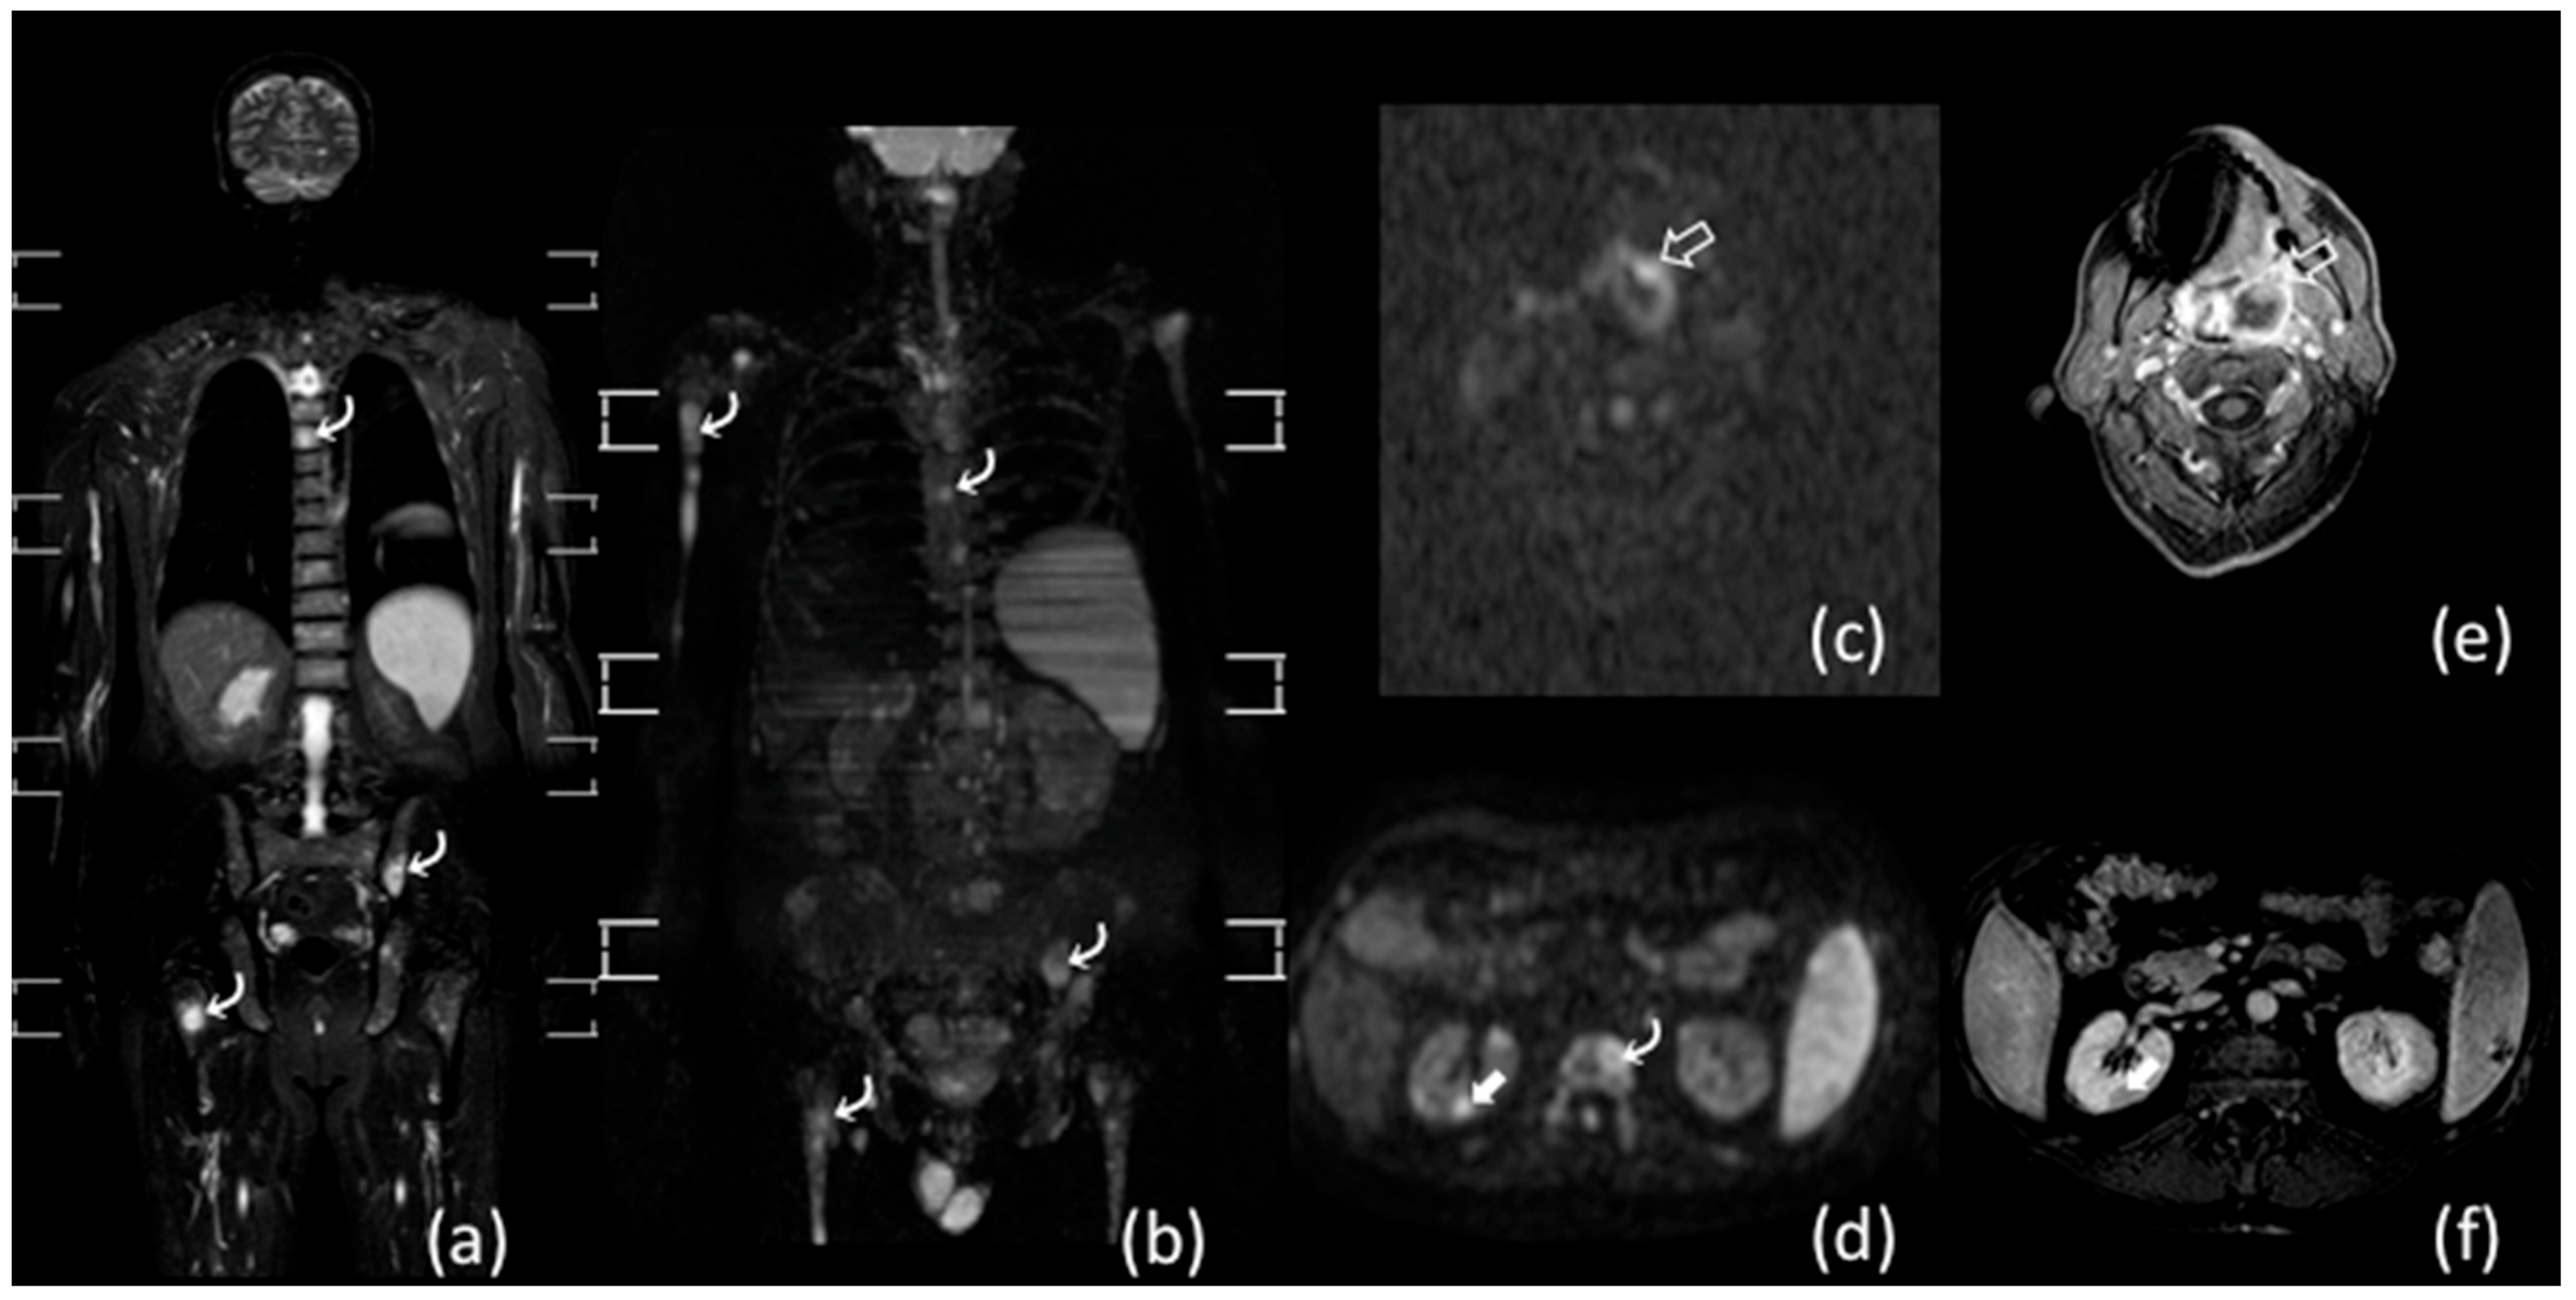

- Albano, D.; Patti, C.; La Grutta, L.; Agnello, F.; Grassedonio, E.; Mulè, A.; Cannizzaro, G.; Ficola, U.; Lagalla, R.; Midiri, M.; et al. Comparison between whole-body MRI with diffusion-weighted imaging and PET/CT in staging newly diagnosed FDG-avid lymphomas. Eur. J. Radiol. 2016, 85, 313–318. [Google Scholar] [CrossRef] [PubMed]

- Lin, C.; Luciani, A.; Itti, E.; El-Gnaoui, T.; Vignaud, A.; Beaussart, P.; Lin, S.-J.; Belhadj, K.; Brugières, P.; Evangelista, E.; et al. Whole-body diffusion-weighted magnetic resonance imaging with apparent diffusion coefficient mapping for staging patients with diffuse large B-cell lymphoma. Eur. Radiol. 2010, 20, 2027–2038. [Google Scholar] [CrossRef]

- Abdulqadhr, G.; Molin, D.; Astrom, G.; Suurkula, M.; Johansson, L.; Hagberg, H.; Ahlström, H. Whole-body diffusion-weighted imaging compared with FDG-PET/CT in staging of lymphoma patients. Acta Radiol. 2011, 52, 173–180. [Google Scholar] [CrossRef]

- Kwee, T.C.; Vermoolen, M.A.; Akkerman, E.A.; Kersten, M.J.; Fijnheer, R.; Ludwig, I.; Beek, F.J.; van Leeuwen, M.S.; Bierings, M.B.; Bruin, M.C.; et al. Whole-body MRI, including diffusion-weighted imaging, for staging lymphoma: Comparison with CT in a prospective multicenter study. J. Magn. Reson. Imaging 2014, 40, 26–36. [Google Scholar] [CrossRef]

- Balbo-Mussetto, A.; Cirillo, S.; Bruna, R.; Gueli, A.; Saviolo, C.; Petracchini, M.; Fornari, A.; Lario, C.; Gottardi, D.; De Crescenzo, A.; et al. Whole-body MRI with diffusion-weighted imaging: A valuable alternative to contrast-enhanced CT for initial staging of aggressive lymphoma. Clin. Radiol. 2016, 71, 271–279. [Google Scholar] [CrossRef] [PubMed]

- Stecco, A.; Buemi, F.; Quagliozzi, M.; Lombardi, M.; Santagostino, A.; Sacchetti, G.M.; Carriero, A. Staging of Primary Abdominal Lymphomas: Comparison of Whole-Body MRI with Diffusion-Weighted Imaging and18F-FDG-PET/CT. Gastroenterol. Res. Pr. 2015, 2015, 1–8. [Google Scholar] [CrossRef] [PubMed]